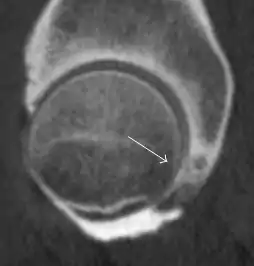

Most of the angles and measurements described in the plain radiograph section can be accurately reproduced on MRI. In addition, the superiority of MRI resolution with intra-articular contrast allows detection of labral and chondral abnormalities that may influence the choice of medical, percutaneous, or surgical management (Figure 9).[1]

Figure 9:

MR arthrography has proven superior in accuracy when compared to native MR imaging. It is considered the best technique to assess the labrum. Knowledge of the normal variable morphology of the labrum helps to differentiate tears from normal variants. A triangular shape is most commonly seen in 66% of asymptomatic volunteers, but round, flattened, and absent labra can also be found in asymptomatic populations. MR arthrography has demonstrated sensitivity over 90% and specificity close to 100% in detecting labral tears. Loose bodies are demonstrated as filling defects surrounded by the hyperintense gadolinium.[1]

Association between labral tears and chondral damage has been demonstrated. This underscores the interaction between cartilage and labrum damage in the progression of osteoarthritis. Chondral damage to the posteroinferior part of the acetabulum as a contrecoup lesion occurs in approximately one-third of pincer cases secondary to persistent abutment on the anterior part of the joint leading to a slight posteroinferior subluxation. This is considered a bad prognosis sign.[1]

MR arthrography can also demonstrate ligamentum teres rupture or capsular laxity, which are debated causes of microinstability of the hip. Elongation of the capsule or injury to the iliofemoral ligament or labrum may be secondary to microtrauma in athletes. MR can demonstrate abnormalities in these cases, such as increased joint volume or a ligamentum teres tear (Figure 9).[1]